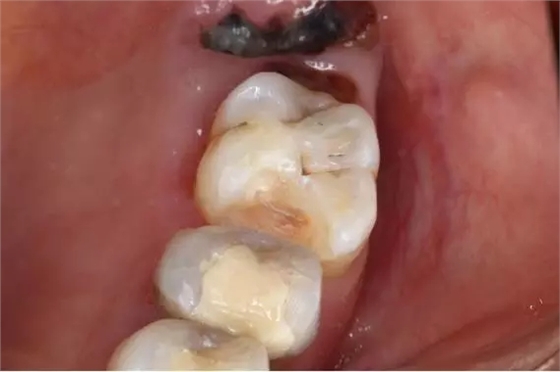

16.涂阻氧劑,繼續(xù)光照

640.webp (15).jpg

17.成品

椅旁修復(fù)病例的完成,給文彬口腔門診部的患者都帶來不一樣的體驗,提高了效率的同時也節(jié)省患者的時間。數(shù)字化是未來的趨勢,即刻修復(fù)一定會越做越多,越做越好。